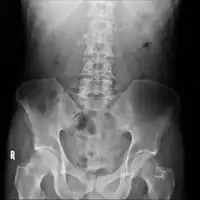

On CT scan, pancreatic and bile duct dilatation, atropy of pancreas, multiple calcifications of the pancreas, and enlargement of pancreatic glands can be found.[12]